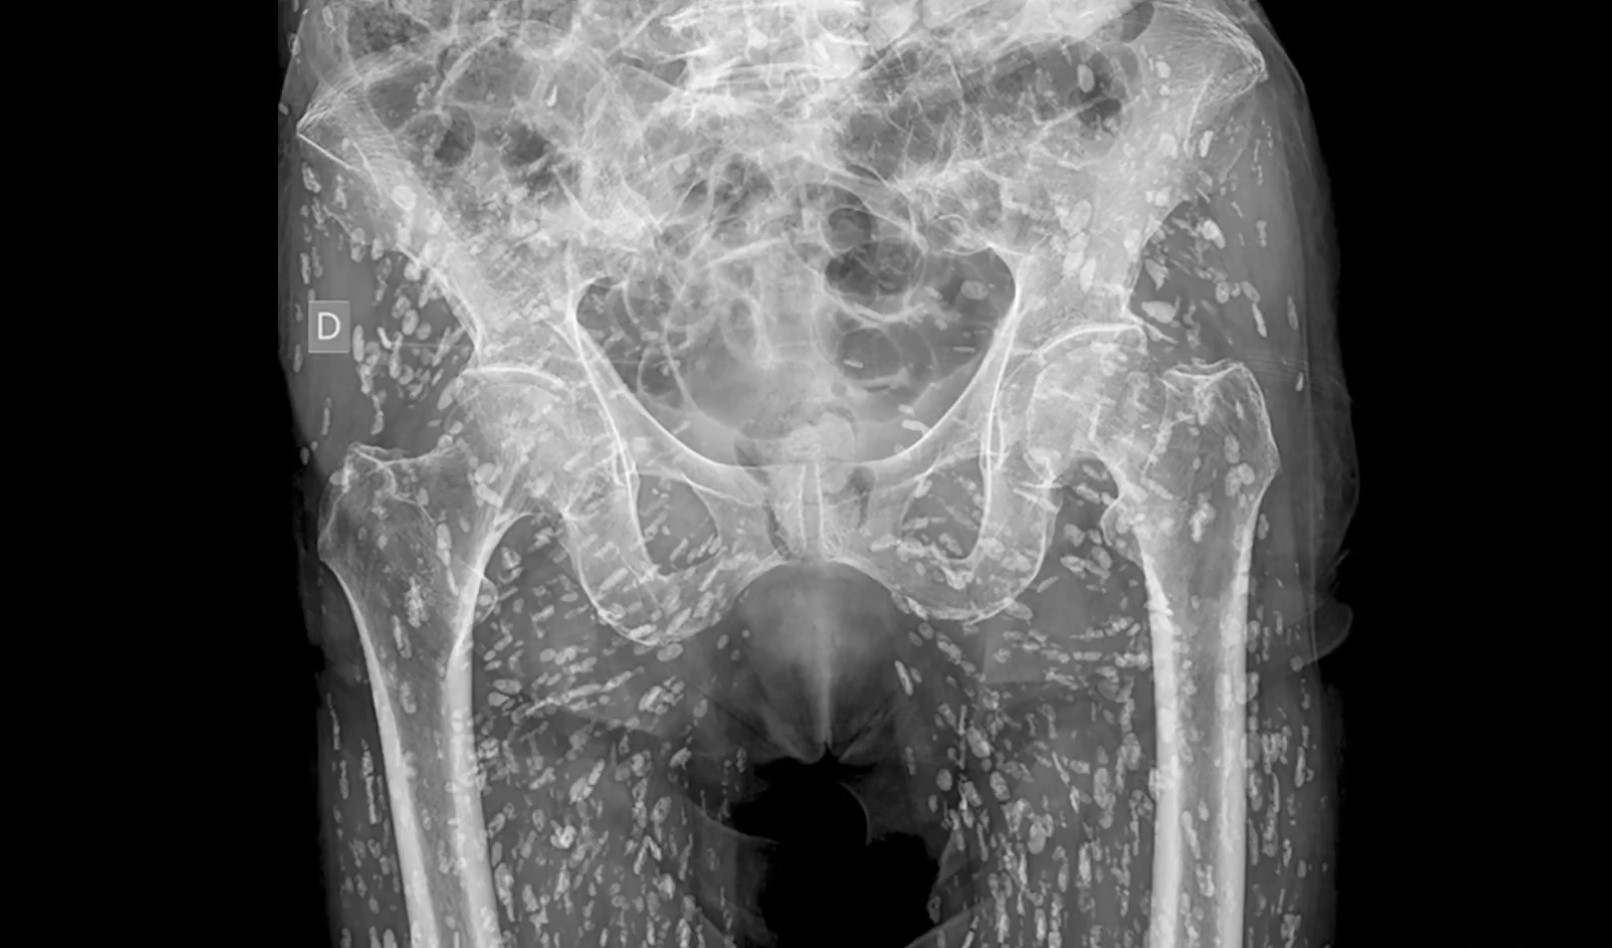

Αντιμέτωπος με μια τρομακτική ανακάλυψη ήρθε ένας άνδρας, όταν διαπίστωσε ότι το σώμα του ήταν γεμάτο από αυγά του παράσιτου tapeworm, όταν μια ακτινογραφία αποκάλυψε εκατοντάδες οζίδια που θύμιζαν κόκκους ρυζιού.

Αυτά τα οζίδια αποδείχθηκαν να είναι κύστες, αποτέλεσμα μιας παρασιτικής λοίμωξης. Ο γιατρός Σαμ Γκάλι στη Φλόριντα, ανέβασε την τρομακτική εικόνα στα μέσα κοινωνικής δικτύωσης, χαρακτηρίζοντας την ως μία από τις «πιο τρελές ακτινογραφίες» που είχε δει ποτέ.

Ο Γκάλι, σε κατάσταση σοκ, δήλωσε σε βίντεο που έγινε viral και έχει συγκεντρώσει περίπου 15 εκατομμύρια προβολές: «Είναι παντού [οι κύστες] και είναι αναρίθμητες, δεν μπορείτε καν να αρχίσετε να τις μετράτε όλες».

Ο γιατρός εξήγησε ότι αυτές οι κύστες μπορεί να μετακινηθούν σε διάφορα μέρη του σώματος, και ότι σε αυτή την περίπτωση είχαν «ταξιδέψει» κυρίως στους μαλακούς ιστούς της λεκάνης και των ποδιών του ασθενούς.